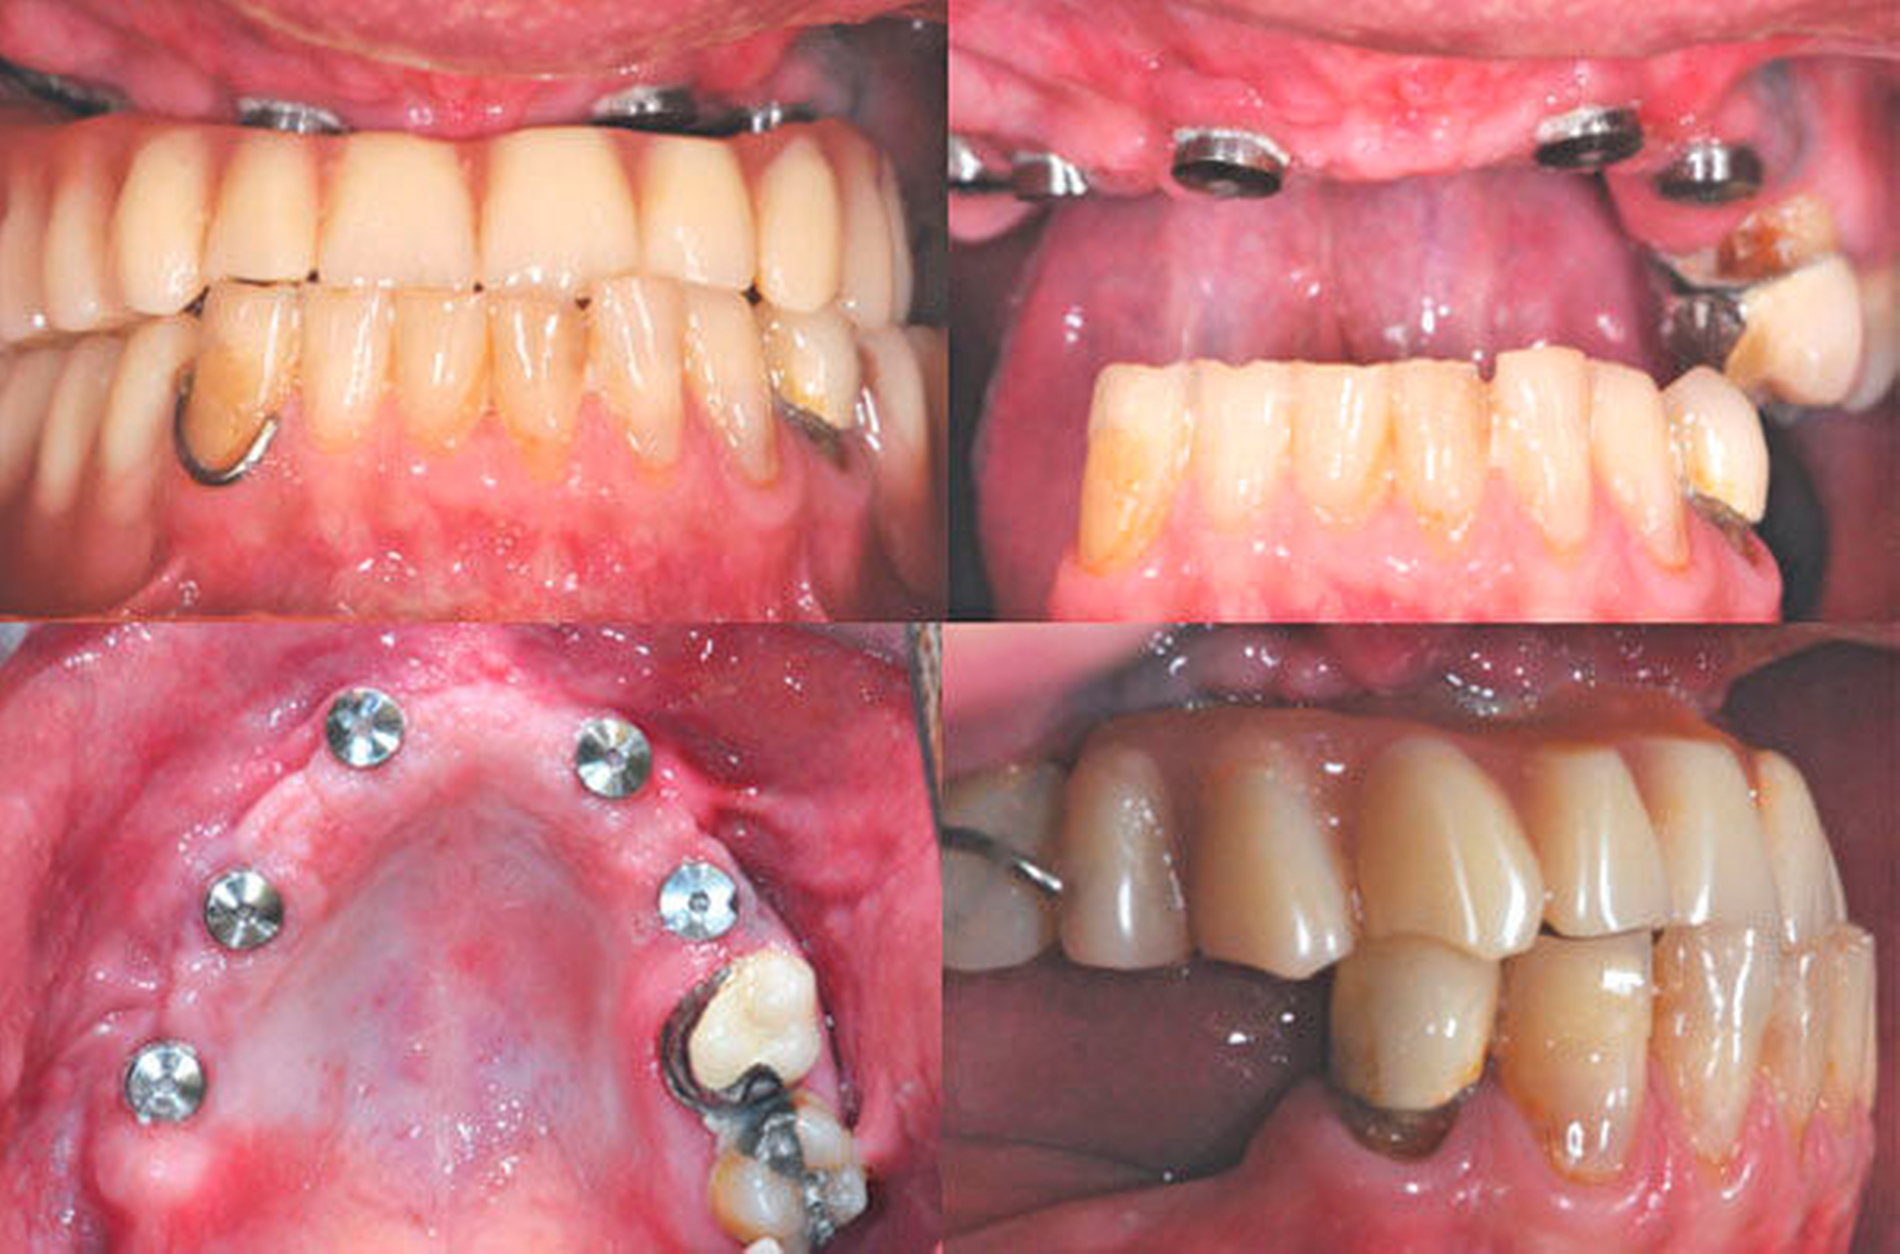

Die klinische Situation zeigte einen atrophierten, teilbezahnten Oberkiefer (herausnehmbarer, nicht implantatgetragener Zahnersatz) sowie einen teilbezahnten Unterkiefer (herausnehmbarer, mit Klammern verankerter Interimszahnersatz) (Abbildung 1). Vor allem fiel der prothetisch eingestellte Kopfbiss im Frontzahnbereich mit ausgeprägter negativer sagittaler Stufe bei einer Rücklage des Oberkiefers von 0,8 cm auf. In der alio loco angefertigten prä-implantologischen Röntgendiagnostik mittels Panoramaschichtaufnahme war dies nicht zu erkennen. Aufgrund des klinischen Bildes eines defizitären Mittelgesichtsprofils erfolgte eine kephalometrische Analyse. Hier bestätigten die ermittelten Werte eine maxilläre Retrognathie (Angle-Klasse III; Abbildung 2).

Insgesamt lag somit eine prothetisch schwierig zu versorgende Situation vor, weshalb nach ausführlicher interdisziplinärer Besprechung gemeinsam mit dem Patienten die Entscheidung zugunsten einer Le-Fort-I-Osteotomie zur Behebung der sklelettalen Fehlstellung und zur Verbesserung des Gesichtsprofils getroffen wurde. Simultan konnten die in situ befindlichen Implantate für den provisorischen Zahnersatz im Sinne eines Operationssplints genutzt werden. Nach der Modelloperation am Artikulator und der Anfertigung sowie der Eingliederung eines individuellen CAD/CAM-gefrästen temporären Zahnersatzes (Poly-Temp®, ceramill®; Amann Girrbach GmbH, Pforzheim, Deutschland) im Oberkiefer (Abbildung 3) erfolgte die maxilläre Umstellungsosteotomie mittels Osteotomie in Le-Fort-I-Ebene. Die temporäre Restauration sicherte intra- und postoperativ die Kieferrelation und Okklusion (Abbildung 4).